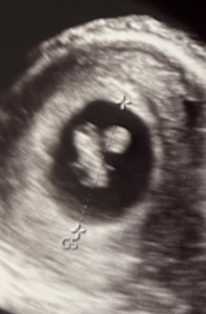

さらに、前回の7w4d、13.2mm時点の写真を見返すと、人型でひょろ長く全身が映っているなという感じ。

卵黄嚢もまん丸く見えます。

対して今回は丸っこく胎芽が見え、卵黄嚢らしきものも楕円形に見えます。

明らかに撮影している角度が違う気がする